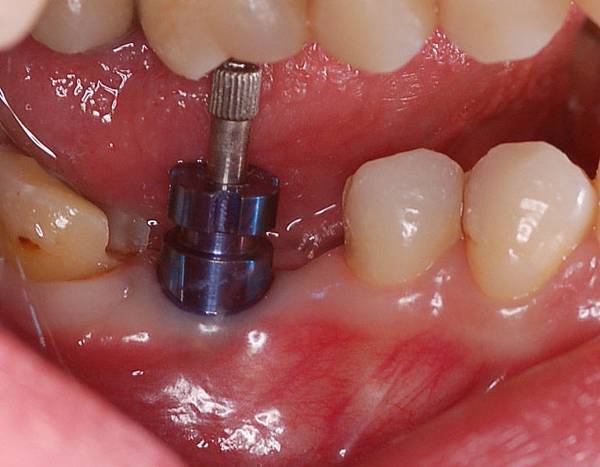

三個月後癒合情形

三個月後癒合情形

側面觀

側面觀

拔牙後同時做植牙動作 三個月後癒合情形

三個月後癒合情形 側面觀